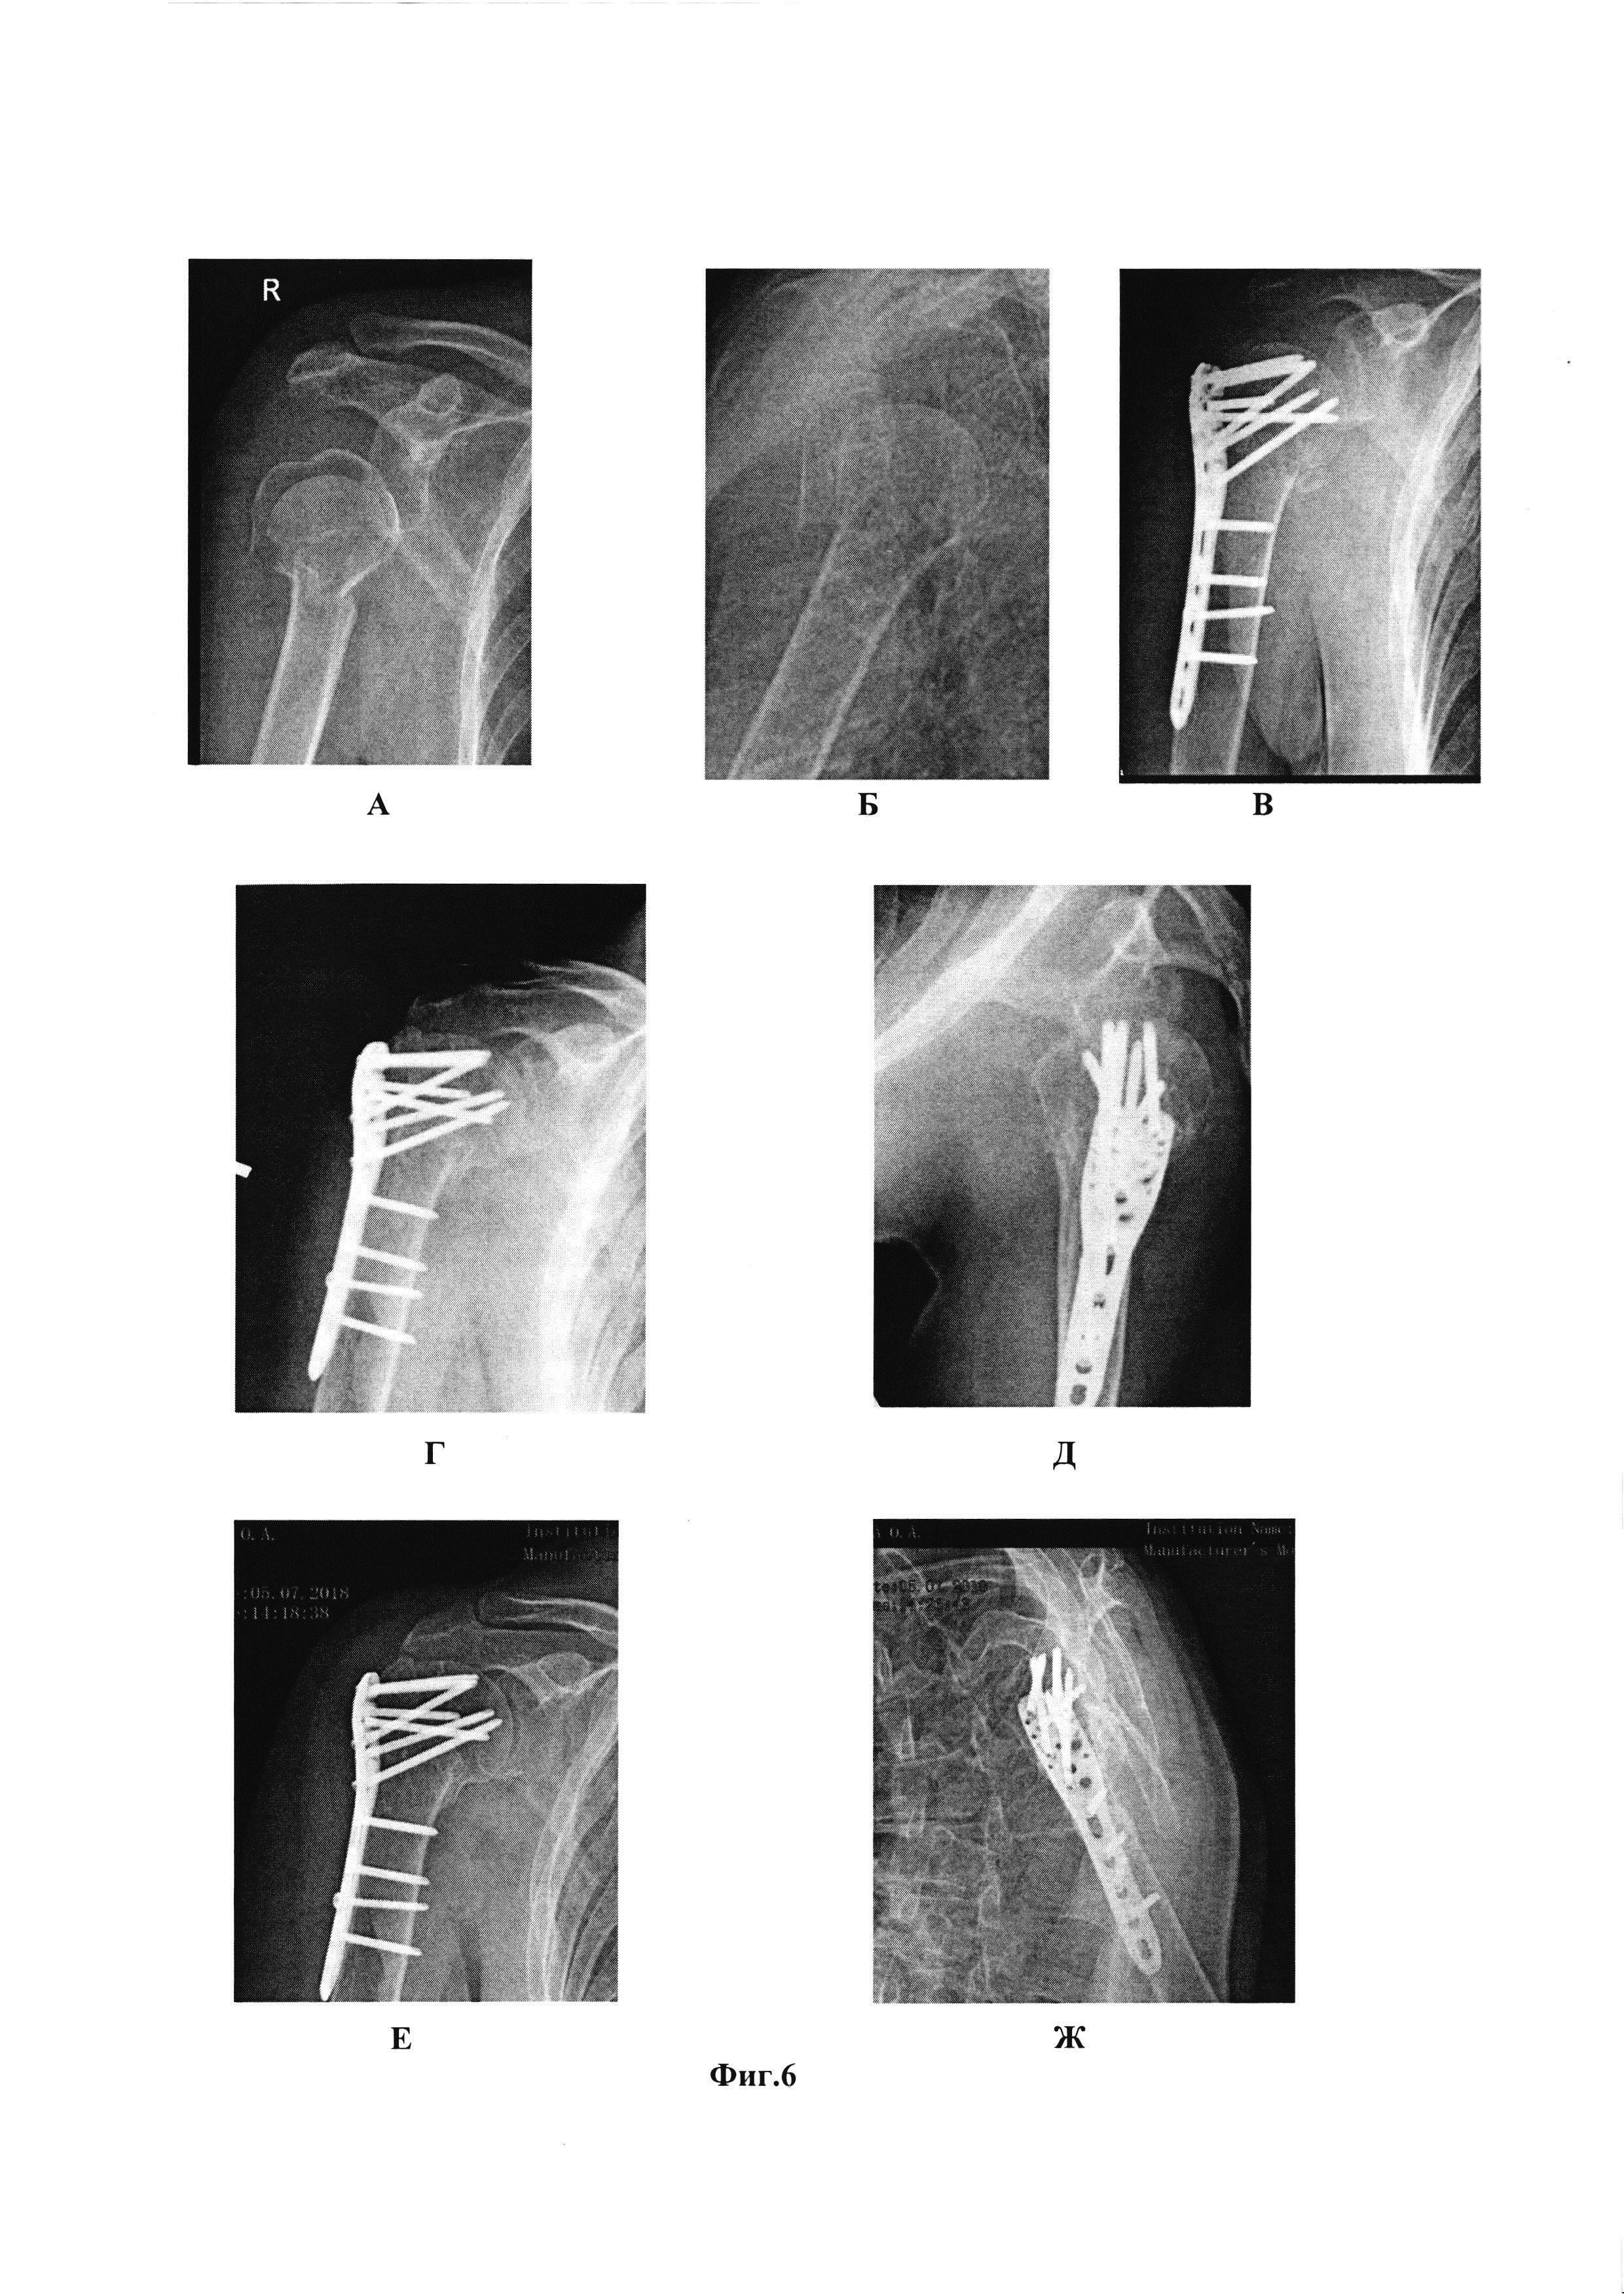

Область техники, к которой относится изобретение Изобретение относится к области медицины, а именно к травматологии, и может быть использовано для репозиции отломков при переломах проксимального отдела плечевой кости. Уровень техники Переломы проксимального отдела плечевой кости составляют около 5-7% от всех переломов у взрослых пациентов и занимают третье место по частоте среди переломов у пожилых пациентов после переломов проксимального отдела бедренной кости и дистального отдела лучевой кости. Переломы проксимального отдела плечевой кости составляют до 75% всех переломов плечевой кости у пациентов старше 60 лет, при этом у женщин они встречаются в 2-3 раза чаще, чем у мужчин [Ломтатидзе Е.Ш., Ломтатидзе В.Е., Поцелуйко С.В. [и др.] Анализ функциональных результатов внутреннего остеосинтеза при переломах проксимального отдела плечевой кости // Вестник травматологии и ортопедии им. Н.Н. Приорова. - 2003. - №3. - С. 62-66.]. Переломы данной локализации оказывают сильное влияние на функцию конечности в ближайшем и отдаленном периодах после травмы. Эпидемиологические исследования говорят о постоянном увеличении числа таких переломов и об удвоении их количества у пациентов в возрасте старше 80 лет в ближайшие 20 лет [Palvanen М., Kannus P., Niemi S., Parkkari J. Update in the epidemiology of proximal humeral fractures. Clin Orthop Relat Res 2006;442:87-92.; Song J.Q., Deng X.F., Wang Y.M., Wang X.B., Li X., Yu B. Operative vs. nonoperative treatment for comminuted proximal humeral fractures in elderly patients: a current metaanalysis. Acta Orthop Traumatol Turc. 2015;49(4):345-53.]. В настоящее время нет однозначных рекомендаций по выбору тактики лечения больных с переломами проксимального отдела плечевой кости. Это связано с большим количеством возможных вариантов лечения: консервативных и оперативных, большого количества модификаций оперативного метода лечения. Важную роль играет время, прошедшее с момента травмы до момента оперативного лечения. Задержка в проведении оперативного лечения более чем на 5 дней приводит к значительному увеличению количества осложнений таких, как аваскулярный некроз головки и вторичное смещение отломков. В случаях с раскалыванием головки плечевой кости и переломов в сочетании с вывихом анатомическая репозиция должна быть выполнена не позднее 48 часов после травмы, это снижает риск аваскулярного некроза головки плечевой кости [ При 3-х и 4-хфрагментарных переломах проксимального отдела плечевой кости неточная репозиция отломков плечевой кости (в частности большого бугорка), высокое стояние пластины и неплотное ее прилегание к кости, а также несостоятельность фиксации в послеоперационном периоде, приводит к развитию субакромиального импинджмента и плохим функциональным результатам лечения. Достижение одновременно правильного положения отломков, правильного позиционирования пластины и плотного ее прилегания к кости является сложной хирургической задачей. В настоящее время существует много способов фиксации отломков при переломах проксимального отдела плечевой кости, однако нет определенного алгоритма действий, который позволил бы добиться четкой анатомической репозиции при любом типе перелома, включая 3-х и 4-хфрагментарные переломы. Наиболее часто для репозиции отломков головки плечевой кости используют спицы в качестве джойстиков для репозиции отломков [Bucholz, Robert W.; Heckman, James D.; Court-Brown, Charles M.; Tornetta, Paul. «Rockwood And Green's Fractures In Adults, 7th Edition». Lippincott Williams & Wilkins. 2010. 1072-1075.]. Недостатком данного метода является сложность позиционирования спиц по причине смещения отломков головки плечевой кости под акромиальный отросток лопатки. Акромиальный отросток лопатки часто ограничивает амплитуду движения спиц-джойстиков, это приводит к необходимости проводить спицы несколько раз, что в свою очередь наносит дополнительную травму кости и окружающим мягким тканям. Кроме того, при проведении интенсивных манипуляций с отломками головки плечевой кости посредством спиц-джойстиков часто происходит их вырывание. Это особенно часто проявляется у пожилых пациентов со сниженной плотностью кости. Каждое вырывание спицы приводит к потере репозиции и требует повторного заведения джойстика. Потеря фиксации спицы-джойстика в кости (при ее вырывании) приводит к формированию костной полости в месте ее установки. Кроме того, частое перепроведение спиц-джойстиков приводит к дополнительной травме кости и окружающих мягких тканей, увеличению количества полостей в кости, уменьшению суммарной костной плотности головки плечевой кости (что особенно ощутимо при проведении остеосинтеза в условиях остеопороза или остеопении). Создание дополнительных костных полостей после спиц-джойстиков приводит к сложности окончательной фиксации перелома с помощью пластин, так как уменьшает фиксационные возможности винтов. Прошивание сухожилий мышц вращающей манжеты плеча (ВМП) рекомендуется многими авторами, как для репозиции, так и для усиления фиксации перелома. Однако рекомендации по тактике последовательности действий разнятся. Так Архипов С.В. и Ковалерский Г.М. прошивание сухожилий мышц вращающей манжеты плеча используют для репозиции отломка большого или малого бугорков, после чего осуществляют временную фиксацию отломков головки плечевой кости спицами Киршнера (2-3 спицы), одновременно с этим производят спицевую фиксацию проксимального отдела плеча к диафизу. После достижения временной фиксации позиционируют пластину, производят окончательную фиксацию перелома пластиной и удаляют провизорные спицы [Архипов С.В., Ковалерский Г.М. Хирургия плечевого сустава. Москва 2015 г. 171-173.]. Авторами также предлагается проведение компрессирующих винтов для достижения плотного контакта пластины с костью, а отверстия в пластине авторы используют для установки проволочных петель с целью дополнительной фиксации мелких отломков. Недостатком данного способа является предварительная фиксация отломков спицами (2-3 иногда и более). Проведение провизорных фиксирующих спиц в дальнейшем создает помехи для уложения и позиционирования пластины. Проведенные провизорные спицы часто проходят через зону максимальной костной массы отломка. Пластину приходится укладывать в обход спиц, это приводит к тому, что блокируемые винты, проходящие через пластину и фиксирующие отломки, идут через зону меньшей косной массы отломка. Перепроведение же спиц приводит к потере временной репозиции и к смещению отломков. Подшивание к пластине сухожилий только подостной и надостной мышц, без обязательного прошивания подлопаточной мышцы создают дисбаланс в плотности прилегания пластины к кости. Из уровня техники для фиксации переломов проксимального отдела плечевой кости известно использование пластин с прошиванием сухожилий мышц ВМП для репозиции отломков бугорков. При этом вначале проводят прошивание сухожилий, потом нити продевают через пластину, производят репозицию и фиксацию пластины к кости [Nho S.J., Brophy R.H., Barker J.U., Cornell C.N., & Macgillivray J.D. Innovations in the management of displaced proximal humerus fractures. The Journal of the American Academy of Orthopaedic Surgeons, 15 1 (2007), 12-26.]. Однако, прошивание сухожилий ВМП нитями только при наличии перелома в точке фиксации создает дисбаланс сил при натяжении этих нитей (то есть при репозиции отломков), что усложняет процесс позиционирования пластины. К этому же приводит и отсутствие центральной спицы, которая центрирует пластину и тем самым осуществляет плотное прижатие (правильно позиционированной) пластины к кости. Основная проблема, с которой встречается хирург при репозиции отломков и позиционировании пластины, это сложность достижения правильной и минимально травматичной репозиции отломков без помех для укладки пластины. Из уровня техники известно использование прошивания сухожилий мышц ВМП и их подшивание к пластине для увеличения прочности фиксации. Однако прошиваются только сухожилия, крепящиеся к сломанным фрагментам (сухожилия надостной и подостной мышц при переломах большого бугорка, сухожилие подлопаточной мышцы при переломах малого бугорка). Для репозиции же авторы используют большое количество спиц Киршнера и зажимы (в частности зажим Лоумена) [Lynn A. Crosby, Robert J.Neviaser Proximal humerus fractures. Evaluation and management. Springer. 2015. 99-105.]. Применение большого количества спиц Киршнера, как уже было сказано, усложняет позиционирование пластины и проведение через нее винтов. Использование для репозиции зажимов наносит дополнительную травму окружающим мягким тканям, и имеет риск повреждения огибающих плечевую кость артерий (в частности задней огибающей) и подмышечного нерва. Наиболее близким к заявляемому решению является способ остеосинтеза при переломе проксимального отдела плечевой кости (Патент на изобретение №2673146), в котором для репозиции отломков плечевой кости используют прошивание сухожилий мышц ВМП, для фиксации - штифт. Способ согласно изобретению осуществляют следующим образом. Выполняют разрез кожи и подкожной жировой клетчатки длиной 5-6 см между передним и средним пучками дельтовидной мышцы от переднелатерального угла акромиона до проекции подмышечного нерва. Разводят дельтовидную мышцу. Прошивают отдельными нитями сухожилия надостной, подостной и подлопаточной мышц, по меньшей мере, двумя стежками каждое, причем сухожилия надостной и подостной мышц прошивают на расстоянии 1-1,5 см от мест их прикрепления к большому бугорку плечевой кости, а сухожилие подлопаточной мышцы - на расстоянии 1-1,5 см от места его прикрепления к малому бугорку плечевой кости. Репозицию отломков проводят путем тракций за концы проведенных через сухожилия нитей, при этом сначала проводят репозицию большого бугорка путем тракций в латеральном и дистальном направлениях за концы нитей, проведенных через сухожилия надостной и подостной мышц, затем ротируют головку плечевой кости путем тракций в дорсальном направлении за концы нити, проведенной через сухожилие подлопаточной мышцы. Сохраняя тягу за нити, выполняют продольный разрез длиной 1-1,5 см сухожилия надостной мышцы, через который формируют в головке плечевой кости входное отверстие для штифта. После введения штифта его фиксируют с помощью блокирующих винтов, проводимых через отверстия штифта, причем проксимальные блокирующие винты проводят через большой и малый бугорки плечевой кости, а дистальный блокирующий винт - через диафиз плечевой кости. К шляпкам винтов фиксируют с натяжением проведенные через сухожилия нити, при этом к винтам, расположенным в области большого бугорка плечевой кости, фиксируют нити, проведенные через сухожилия надостной и подостной мышц, а к винту, проведенному через малый бугорок плечевой кости, фиксируют нити, проведенные через сухожилие подлопаточной мышцы. Способ позволяет уменьшить травматичность и длительность вмешательства, повысить надежность репозиции, предотвратить нарушение кровоснабжения головки плечевой кости. Однако для того чтобы прошить все перечисленные сухожилия, хирургу необходимо произвести достаточно широкий хирургический доступ. Хирургический доступ через дельтовидную мышцу ограничен снизу анатомическим ходом подмышечного нерва. Существующий трансдельтовидный доступ должен проходить не далее 5 см ниже акромиона, иначе существует риск повреждений ствола подмышечного нерва. Расположение подмышечного нерва ориентировочное и существуют анатомические особенности, которые могут приводить к более высокому расположению нерва. Чем шире хирургический доступ, тем выше риск повреждения подмышечного нерва. При этом в передних отделах подмышечный нерв представлен уже не в виде четкого ствола, а в виде множества ветвей, которые иннервируют переднюю порцию дельтовидной мышцы. Производя широкое разведение дельтовидной мышцы (на 5-6 см от акромиона) хирурги пересекают все мелкие, идущие к передней части дельтовидной мышцы, пучки нервов. Это приводит к денервации и атрофии передней порции дельтовидной мышцы. Чем меньше разводятся пучки дельтовидной мышцы, тем больше мелких ветвей подмышечного нерва будет сохранено. Кроме того, предложенная последовательность прошивания сухожилий надостной, подостной и подлопаточной мышц, по меньшей мере, отдельными нитями с двумя стежками каждое, является менее удобной, зачастую приводящая к применению дополнительных устройств для доступа к сухожилию надостной мышцы, т.к. после переломов, смещение отломков таково, что сухожилие надостной мышцы уходит часто глубоко под акромион и физически вытащить его от туда для прошивания без специальных приспособлений (спиц, элеваторов и т.д.) не возможно. Кроме того, способ репозиции фрагментов кости в известном решении сопряжен с высоким риском их смещения при введении импланта, в связи с тем, что после прекращения тракций за нити отломки возвращаются на место под действием силы мышц, и при введении штифта нет центра приложения сил во время тракций. При этом установка проксимальных блокирующих винтов подразумевает наличие громоздких направителей, которые мешают сохранению тракций за джойстики. Кроме того, фиксация нитей «джойстика» к шляпкам винтов также имеет свои недостатки. Шляпки винтов для блокирующего штифта имеют бочкообразный вид. При введении винтов плотно к кости, места для накидывания на головку винта нити совсем не остается. Это может приводить к соскакиванию нити со шляпки винта и ослаблению фиксации. Недовведение винта до кости для облегчения фиксации нити вокруг него может приводить к субакромиальному импинджменту (соударению шляпки винта и акромиального отростка лопатки). Помимо этого, прикрепление нитей от надостной и подостной мышц к винту фиксирующему большой бугорок (точку прикрепления этих мышц), а от сухожилия подлопаточной мышцы к винту, проведенному через малый бугорок, увеличивает вырывающую силу, приложенную к винту. Кроме того, данный вид остеосинтеза можно применять только в ранние сроки после травмы. Через 5-7 дней формирующиеся между отломками рубцы не позволят произвести точную репозицию отломков по данной методике, или потребуют дополнительных хирургических доступов. Так же дополнительную травму суставу наносит разрез надостной мышцы (1-1,5 см) для формирования канала для введения штифта. Решаемой технической проблемой является разработка технически несложного, анатомичного и малотравматичного способа остеосинтеза переломов проксимального отдела плеча, включая 3-х и 4-х фрагментарные переломы, переломы в условиях снижения костной плотности, путем остеосинтеза их пластиной, обеспечивающего адекватную репозицию отломков, их надежную фиксацию и профилактику вторичного смещения в любые сроки после травмы. Раскрытие сущности изобретения Техническим результатом, на достижение которого направлено заявленное изобретение, является обеспечение надежной фиксации отломков как при простых 2-х фрагментарных, так и при тяжелых 3-4 фрагментарых переломах проксимального отдела плечевой кости, на любых сроках после травмы, при минимизации риска развития осложнений, обусловленных оперативным вмешательством. Технический результат достигается за счет реализации способа остеосинтеза при переломе проксимального отдела плечевой кости, включающий хирургический доступ к плечевому суставу, прошивание отдельными нитями сухожилий надостной, подостной и подлопаточной мышц с последующей репозицией отломков посредством тракций за концы проведенных через сухожилия нитей, после чего проводят остеосинтез с использованием импланта с фиксацией концов нитей к импланту и фиксацией импланта к плечевой кости блокирующими винтами, при этом: - к плечевому суставу осуществляют дельтопекторальный доступ с разрезом кожи и подкожной жировой клетчатки между дельтовидной и большой грудной мышцами; - в качестве импланта используют пластину с отверстиями для проведения блокирующих винтов для остеосинтеза проксимального отдела плечевой кости; - прошивание сухожилий проводят сначала подлопаточной мышцы, затем надостной и подостной; - после прошивания сухожилий концы нитей продевают через предназначенные для проведения нитей отверстия в пластине, центрируют пластину относительно суставной поверхности плечевой кости, после чего в центральное отверстие в пластине устанавливают центральную спицу, с последующей репозицией отломков путем тракций за концы нитей, удерживая пластину с проведенной центральной спицей; - концы нитей фиксируют к отверстиям в пластине. Прошивание сухожилий подлопаточной, надостной и подостной мышц проводят нерассасывающимися нитями (Терилен 5, FiberWire 2 и др.) на расстоянии 1 см от места прикрепления сухожилия к точке фиксации (большому или малому бугорку), как показано на фиг. 1, 2. При этом каждое сухожилие прошивают нитью крестообразным швом с двукратным пересечением под прямым углом лини шва, расположенной параллельно соответствующей торцевой стороне пластины, с выводом концов нитей с внешней стороны сухожилия. Прошивание осуществляют в последовательности 1-6, указанной на фиг. 1. В способе используют предизогнутую пластину для проксимального отдела плечевой кости. Оперативный доступ производят через стандартный дельто-пекторальный доступ. Выполняют разрез кожи и подкожно-жировой клетчатки начиная от клювовидного отростка лопатки до в/3 плеча длинной 15 см., находят v.cephalica, и отводя ее латерально осуществляют доступ между дельтовидной и большой грудной мышцами к плечевому суставу. Для проведения репозиции концы нитей идущих от сухожилий продевают через отверстия в пластине, соответствующие направлению хода волокон сухожилия: нити, идущие от подлопаточной мышцы продевают через отверстия на переднем краю пластины, нити от надостной мышцы - через задне-верхние отверстия в пластине, нити от подостной мышцы - через отверстия, расположенные по заднему краю пластины. Центрируют пластину после продевание нитей через отверстия в пластине под электронно-оптическим преобразователем, ориентируясь на суставную поверхность плечевой кости так, чтобы угол между плоскостью суставной поверхности и продольной осью пластины соответствовал шеечно-диафизарному углу плечевой кости, после чего устанавливают центральную спицу, проходящую через центр пластины и центр головки плечевой кости, при этом добиваются правильного угла наклона суставной поверхности головки плечевой кости к продольной оси пластины (оптимально 130°). Репозицию отломков путем тракций за концы нитей осуществляют посредством натяжения нитей (всех 3 нитей одновременно), фиксирующих ВМП, прижимая пальцем пластину к проксимальному отделу плечевой кости. При этом сначала производится натяжение нитей и только потом, при натянутых нитях, осуществляют прижатие пластины к уже репонированным отломкам плечевой кости. Эта манипуляция позволяет добиться быстрой и качественной репозиции отломков и обеспечить плотное прилегание пластины к кости. Пластину фиксируют к проксимальному отделу плечевой кости блокируемыми винтами. Удерживают нити и плотно прижимают пластину к кости, производят рассверливание по направителю наиболее удобных для вкручивания винтов отверстий. После чего фиксируют пластину винтами. Первыми используют отверстия, находящиеся в верхне-переднем квадрате пластины, так как они просты в установке из имеющегося хирургического доступа и позволяют зафиксировать пластину изолированно к проксимальному отделу кости. Проведя проксимальные винты, фиксируют пластину к диафизу кости через овальное отверстие кортикальным винтом 3,5 мм, позиционируя передний край пластины позади сухожилия длинной головки двухглавой мышцы. Контролируют положение отломков на ЭОП. Фиксацию концов нитей к отверстиям в пластине осуществляют путем поочередного завязывание нитей. Первым фиксируют к пластине сухожилие подлопаточной мышцы. В положении внутренней ротации плеча нити завязываются на 6 узлов. Далее в положении отведения и наружной ротации плеча фиксируют так же 6-ю узлами сухожилие надостной мышцы. Последним этапом, в положении наружной ротации плеча фиксируют к пластине сухожилие подостной мышцы. Так как длина кортикального винта которым изначально фиксируется диафиз кости часто велика, то он в дальнейшем его заменяют на более короткие блокирующие винты. Кроме того, данный способ остеосинтеза осуществим на любых сроках после травмы, не требует дополнительного разреза сухожилия надостной мышцы, и производится через анатомически безопасный интервал между мышцами (дельтовидной и большой грудной), исключающий повреждение дельтовидной мышцы (как основной силы осуществляющей движения в плечевом суставе). Таким образом, в заявляемом решении в отличие от способа - прототипа, выполняют дельтопекторальный доступ, который осуществляется между дельтовидной и большой грудной мышцами, который позволяет осуществить широкий хирургический доступ к плечевому суставу, без риска послеоперационных неврологических осложнений. Прошивание первым этапом сухожилия подлопаточной мышцы и тракция за данный джойстик позволяет «вытащить» сухожилие надостной мышцы из-под акромиона и значительно более проще прошить сухожилия, не используя металлические инструменты. Репозиция отломков осуществляется одновременно с их фиксацией к пластине, тем самым нет риска их смещения при введении импланта. Наличие центральной спицы создает вектор приложения всех сил, который направлен к пластине. За счет одновременной тракций за джойстики и прижимания пластины к кости создается репозиционный момент, который способствует одновременной репозиции всех сухожилий и отломков. Фиксация отломков в пластине происходит без громоздких направителей, что облегчает сохранение натяжение нитей и сохранение репозиции отломков. Фиксация нити в отверстии в пластине (по сравнению с прототипом, где фиксация осуществляется к шляпкам винтов) является значительно более надежной, при этом отсутствует риск ослабления фиксации. Поочередное прошивание всех сухожилий мышц ВМП независимо от наличия перелома костного фрагмента в точке прикрепления позволяет реализовать репозицию отломков с помощью нерассасывающихся нитевых джойстиков. Репозиция достигается с помощью установки центральной спицы и баланса между нитевыми джойстиками. Центральная спица, а также обязательное прошивание всех трех сухожилий мышц ВМП позволяет правильно распределить силы при репозиции, при этом не смещая пластину (из-за дисбаланса нитей). Дисбаланс нитей, может развиваться, во-первых, при их наложении не за все три сухожилия. Во-вторых, даже при наложении нитей за все три сухожилия, при отсутствии центральной спицы, тракция за нити приводит к смещению пластины кверху и кзади. Попытки одновременно удержать пластину в правильном положении и соблюсти баланс между нитями приводят или к недонатяжению нитей (и возможно к недорепозиции отломков) или к нарушению положения пластины (больше кверху и кзади, что может приводить к субакромиальному импинджмент синдрому). Подтягивание сухожилия мышц ВМП к пластине (при натягивании нитевых джойстиков) позволяет поставить костный отломок большого бугорка под пластину, тем самым обеспечивая его плотное прижатие последней после выполнения окончательного остеосинтеза и в тоже время фиксацию его винтом через зону максимальной костной массы отломка. Разработанная оригинальная последовательность манипуляций позволяет добиться быстрой, точной и надежной репозиции, а также стабильной фиксации при любых типах переломов проксимального отдела плечевой кости (3-х, 4-х фрагментарных, в том числе и условиях остеопороза). При осуществлении способа обеспечивается плотная фиксация пластины к проксимальному отделу плечевой кости, что позволяет минимизировать риск осложнений, например, импинджмета пластиной, так как уменьшается зазор между пластиной и костью и пластина легко заходит в субакромиальное пространство при отведении плеча. Краткое описание чертежей Изобретение поясняется чертежами, где на фиг. 1 представлена схема прошивания подлопаточной мышцы, на фиг. 2 - схема проведения нитей через пластину, на фиг. 3 представлены этапы репозиции отломков проксимального отдела плечевой кости: А -поочередное прошивание сухожилий мышц ВМП, позиционирование пластины, установка центральной спицы, продевание нитей через соответствующие отверстия в пластине; Б, В - натяжение нитей, репозиция отломков; Г, Д - интраоперационные рентгенограммы до и после репозиции: на фиг. 4 - этапы репозиции отломков проксимального отдела плечевой кости: произведена фиксация пластины к проксимальному отделу плечевой кости блокируемыми винтами и фиксация диафиза кортикальным винтом 3,5 мм; на фиг. 5 - конечный этап операции: А, Б - рентгенологический контроль положения отломков и фиксатора; В - вид раны, фиксация нитей к пластине; на фиг. 6 - рентгенограммы, демонстрирующие клинический пример: А и Б - рентгенограммы после травмы; В - после операции; Г и Д - через 3 месяца после операции; Е и Ж - через 6 месяцев после операции, перелом сросся. Осуществление изобретения Последовательность действий по остеосинтезу при переломах проксимального отдела плечевой кости заключается в следующем. Вначале прошивают сухожилия мышц ВМП, затем нити продевают через пластину, далее устанавливают центральную спицу позволяющую центрировать натяжение нитей-джойстиков, и репонировать отломки плечевой кости. Последовательность прошивания сухожилий: вначале прошивают сухожилие подлопаточной мышцы, затем сухожилие надостной мышцы, после чего - сухожилие подостной мышцы. Данная последовательность дает возможность поэтапно достичь репозиции отломков головки плечевой кости. Первый шов проводят через наиболее доступное при переднем дельто-пекторальном доступе сухожилие подлопаточной мышцы. В дальнейшем манипуляция с первым джойстиком-держалкой позволяет достичь частичной репозиции головки плечевой кости и облегчить доступ к сухожилию надостной мышцы, которое находится глубоко в субакромиальном пространстве. Прошивание вторым этапом сухожилия надостной мышцы и манипуляция данным (вторым) джойстиком позволяет получить доступ и прошить еще более тяжело достигаемое (через передний дельтопекторальный хирургический доступ) сухожилие наружного ротатора (подостной мышцы). При использовании пластин для проксимального отдела плечевой кости их отверстия применяются для подшивания к пластине сухожилий мышц вращающей манжеты плеча. Однако данная манипуляция (по рекомендациям производителя) применяется при переломах соответствующих участков плечевой кости (точек прикрепления данных сухожилий). В изобретении предлагается прошивать все три сухожилия мышц независимо от наличия перелома соответствующего фрагмента плечевой кости, т.к. это позволяет достичь правильного баланса сил при репозиции отломков и улучшить плотность прилегания пластины к кости, тем самым увеличивая прочность фиксации перелома. Ниже представлено более детальное описание заявляемого способа. Операцию производят под проводниковой анестезией в положении больного на спине. Укладку больного выполняют эксцентрично относительно продольной оси операционного стола, смещая поврежденное плечо ближе к центру стола. Голову пациента фиксируют дополнительными упорами, электронно-оптический преобразователь располагают со стороны здорового надплечья. Оперативный доступ производят через дельто-пекторальный доступ. Выполняют разрез кожи и подкожно-жировой клетчатки начиная от клювовидного отростка лопатки до в/3 плеча длинной 15 см., находят v.cephalica, и отводя ее латерально осуществляют доступ между дельтовидной и большой грудной мышцами к плечевому суставу. После доступа к плечевой кости, поочередно идентифицируют: большую грудную мышцу, выходящее из-под нее сухожилие длинной головки двухглавой мышцы, короткую головку двухглавой мышцы. Прослеживают сухожилие длинной головки двухглавой мышцы до уровня межбугорковой борозды и идентифицируем большой и малый бугорки плечевой кости. От малого бугорка начинается сухожилие подлопаточной мышцы, которое идет под короткой головкой двухглавой мышцы. Первым этапом находят сухожилие подлопаточной мышцы и прошивают. Прошивание сухожилия подлопаточной мышцы производят нерассасывающимися нитями (например, Терилен 5, FiberWire 2) на расстоянии 1 см от малого бугорка. Далее нити берут на держалку (фиг. 1). Вторым этапом производят прошивание сухожилия надостной мышцы. Для этого идентифицируют акромиально-клювовидную связку, отводят ее вверх, после чего осуществляя тракцию за сухожилие подлопаточой мышцы, находят и выводят для прошивания из под акромиального отростка лопатки сухожилие надостной мышцы. Схема прошивания сухожилия и тип нитей одинаковы для всех сухожилий мышц вращающей манжеты плеча. Причем, чем тоньше и прочнее используемые нити, тем меньшими будут узлы после фиксации сухожилий к пластине. Третьим этапом идентифицируют и прошивают сухожилие подостной мышцы. Сухожилие мышцы крепится к середине заднего края большого бугорка. Для облегчения прошивания сухожилия подостной мышцы используют тракцию за сухожилие надостной мышцы. В результате получают три нитевых джойстика (подлопаточный, надостный и подостный). Данные джойстики позволяют в полном объеме контролировать положение отломков и головки плечевой кости без риска их прорезывания, что часто происходит со спицевыми джойстиками в условиях сниженной костной массы у пожилых людей. Следующим этапом является поочередное продевание нитей, идущих от сухожилий ВМП (вращающей манжеты плеча), через соответствующие отверстия в пластине для проксимального отдела плечевой кости (фиг. 2). Особенностью остеосинтеза 4-х фрагментарных переломов проксимального отдела плечевой кости является проведение костной пластики до использования пластины. Могут быть использованы костные аллотрансплантаты для заполнения дефекта между бугорками и отломком суставной поверхности. Далее производят позиционирование пластины, располагая ее позади межбугорковой борозды и на 5 мм ниже верхнего края большого бугорка. После чего фиксируют пластину одной центральной спицей Киршнера. Установка центральной спицы является важным моментом операции. Данная спица является опорной. Ее наличие позволяет центрированно прижимать пластину при натяжении нитей, в тоже время установка данной центральной спицы определяет вектор репозиции сломанных участков проксимального отдела плечевой кости. Прошивание же сухожилий мышц ВМП, крепящихся к несломанным фрагментам, создает компенсаторные силы, препятствующие искривлению спицы и однобокому (ацентричному) смещению пластины, что также формирует правильный вектор репозиции сломанных фрагментов. Положение пластины проверяют на ЭОП (Электронно-оптическом преобразователе), ориентируясь по расположению центральной спицы. После чего производят натяжение нитей фиксирующих ВМП, прижимая пальцем пластину к проксимальному отделу плечевой кости. Эта манипуляция позволяет добиться быстрой и качественной репозиции отломков и обеспечить плотное прилегание пластины к кости (фиг. 3 А-Д). Следующим этапом является фиксация пластины к проксимальному отделу плечевой кости блокируемыми винтами. Пластину устанавливают накостно, что не требует проведения дополнительного разреза сухожилия надостной мышцы. Удерживая нити и плотно прижимая пластину к кости, производят рассверливание по направителю наиболее удобных для вкручивания винтов отверстий. После чего фиксируют пластину винтами. Первыми следует использовать отверстия, находящиеся в верхне-переднем квадрате пластины, так как они просты в установке из имеющегося хирургического доступа и позволяют зафиксировать пластину изолированно к проксимальному отделу кости. Проведя проксимальные винты, фиксируют пластину к диафизу кости через овальное отверстие кортикальным винтом 3,5 мм, позиционируя передний край пластины позади сухожилия длинной головки двухглавой мышцы. Контролируют положение отломков на ЭОП (фиг. 4). Вкручивание диафизарного винта позволяет добиться правильной репозиции диафиза относительно проксимального отдела кости. Следующим этапом производят затягивание и фиксацию нитей к пластине, удаление центральной спицы и установка дополнительных винтов. При этом подлопаточную мышцу фиксируют через отверстия на переднем краю пластины, надостную мышцу - через задне-верхние отверстия в пластине, подостную мышцу - через отверстия расположенные по заднему краю пластины. Так как длина кортикального винта, которым изначально фиксируется диафиз кости, часто велика, то он в дальнейшем заменяется на более короткие блокирующие винты (фиг. 5). Фиксация отломков пластиной осуществляется по принципам абсолютной стабильности, что позволяет добиться прочной фиксации и начать раннюю реабилитацию. В 2017-2018 годах в отделении неотложной травматологии опорно-двигательного аппарата НИИ скорой помощи им. Н.В. Склифосовского, согласно заявляемому способу было прооперировано 32 пациента (27 женщин и 5 мужчин) старше 60 лет с переломами шейки плечевой кости. Средний возраст пострадавших 71,4 года. Таблица 1. Распределение пациентов с переломами проксимального отдела плечевой кости по полу и типу перелома. Всем больным при поступлении производили рентгенологическое исследование в 2-х проекциях, оценивали индекс кортикального слоя (ИКС) по Tingard, который определяется как среднее арифметическое толщины 4-х кортикальных слоев на стандартных прямых рентгенограммах. Для исследования были отобраны пациенты с пониженной минеральной плотностью кости, у которых ИКС был менее 4 мм. У всех пациентов причиной перелома была низкоэнергетичная травма. Оперативное лечение производили в первые 4-5 дней после травмы. Фиксацию перелома проводили блокируемыми пластинами для проксимального отдела плеча (DC или PHILOS). После проведения остеосинтеза проводили рентгенологическое исследование для оценки качества репозиции (в том числе шеечно-диафизарного угла). В послеоперационном периоде руку фиксировали косыночной повязкой на 5 недель. С 1 дня после операции назначали активную лечебную гимнастику. Количество и интенсивность упражнений увеличивали по мере уменьшения болевого синдрома. Контрольные обследование больных проводили в сроки 1,5; 3 и 6 месяцев. Оценивали жалобы пациентов (в частности интенсивность болевого синдрома), объем движений в плечевом суставе, проводили рентгенологическое исследование в 2-х проекциях и ультразвуковое исследование плечевого сустава. У всех прооперированных пациентов интраоперационно удалось добиться удовлетворительной репозиции и правильного шеечно-диафизарного угла. Оценка результатов лечения. При оценке рентгенологических данных. • Достигнутое интраоперационно положение отломков и шеечно-диафизарный угол сохранялись в течение всего срока наблюдения. • У всех прооперированных пациентов переломы срослись. При оценке данных ультразвукового исследования выявили. Оценка функциональных результатов пациентов прооперированных по вышеуказанной методике. Клинический пример. Пациентка 76 лет. 4-х фрагментарный перелом. Пациентка прооперирована по предложенной методике. Интраоперационно удалось добиться правильного положения отломков. При динамическом наблюдении за пациенткой отмечено сохранение достигнутого положения отломков и отсутствие признаков несостоятельности фиксации. Перелом сросся. Данные УЗИ коррелировали с функцией плечевого сустава. Через 6 месяцев после операции отведение и сгибание были более 170 градусов.